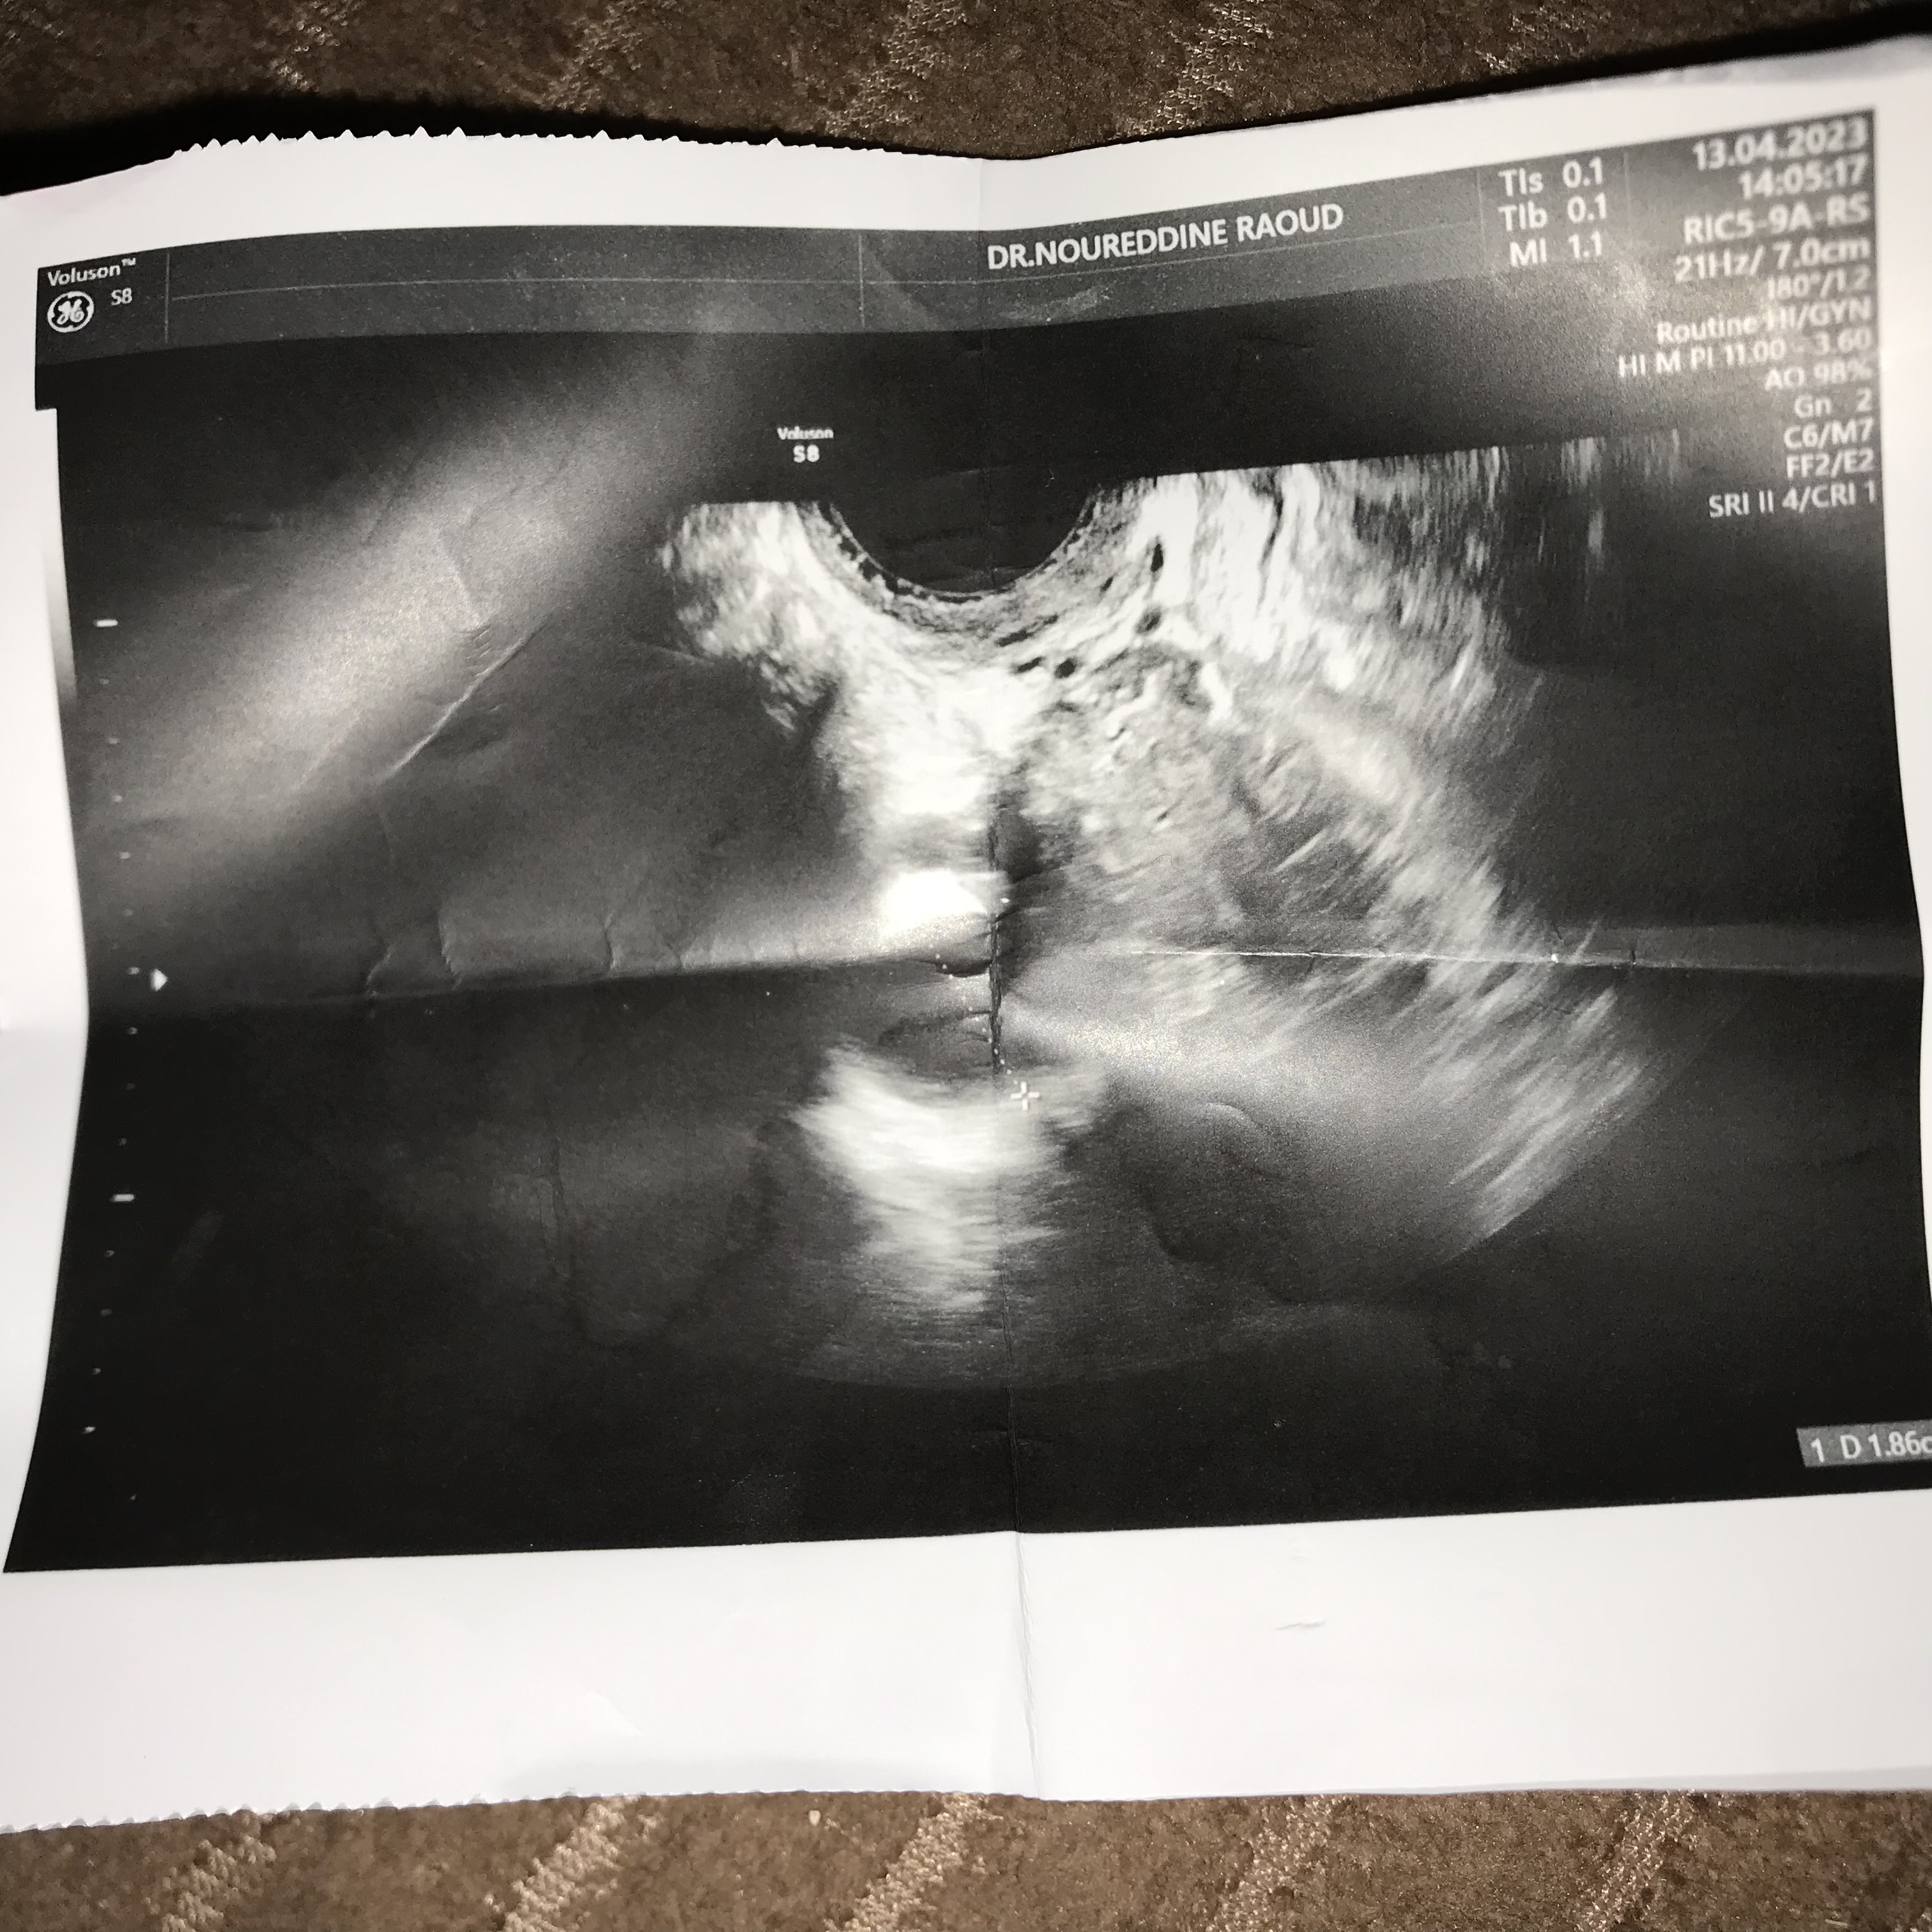

سلام عليكم انا زينب عمري 24سنه